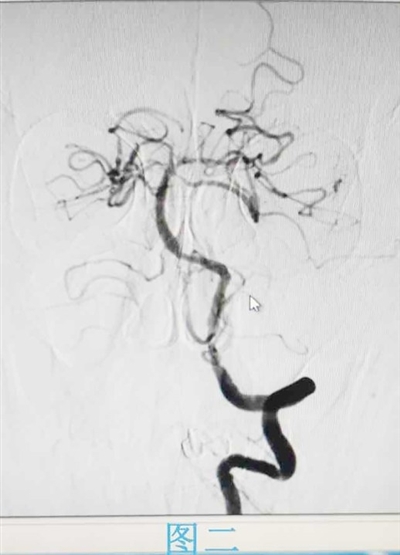

2023年11月30日,27岁患者李猛(化名)因出现中风症状,已不能自行行走和说话。在家人的陪同下,李猛被紧急送到城阳区人民医院急诊神经内科。神经内二科医生一边和家属说明情况,一边开启卒中绿色通道进行诊断检查,并和家属沟通说明检查及治疗的必要性和风险性。经脑核磁所示,李猛被确诊为急性脑梗死,左侧大脑中动脉闭塞。由于已过静脉溶栓时间窗,医生决定进行介入手术,给予其脑动脉内溶栓治疗。在江毅和团队的努力下,李猛成功脱险,言语功能已明显改善,能部分发音。

2023年12月10日,78岁的李涛因言语不清和右侧肢体活动困难被家人紧急送往城阳区人民医院急诊神经内科。医生经查体发现李涛昏睡,双眼向左凝视,右侧鼻唇沟浅,伸舌不合作,且右侧肢体肌力为0级,右侧病理征阳性。经询问家人得知,患者有高血压病和房颤病史。胸部CT结果显示肺气肿、左下肺支气管扩张、右侧斜裂胸膜增厚、冠状动脉钙化和心脏增大,脑CT显示脑萎缩。由于患者患有多种慢性基础性疾病,虽使用阿替普酶溶栓治疗,但大血管闭塞溶栓血管不理想。医生与家属沟通同意后,马上给予手术取栓治疗,立即联系卒中团队,麻醉师、介入科和神经介入医师迅速到位,60分钟后血管再通,经系统治疗后李涛康复出院。

江毅介绍,在卒中中心接诊的患者中,也有不少脑血管重度狭窄的病人。患者张磊因头晕入院,医生对其进行相关检查,通过颈部血管超声显示,张磊左侧锁骨下动脉盗血,完善脑血管造影显示双侧颈内动脉及左侧锁骨下动脉重度狭窄。经过介入支架手术治疗后,张磊恢复良好并出院。